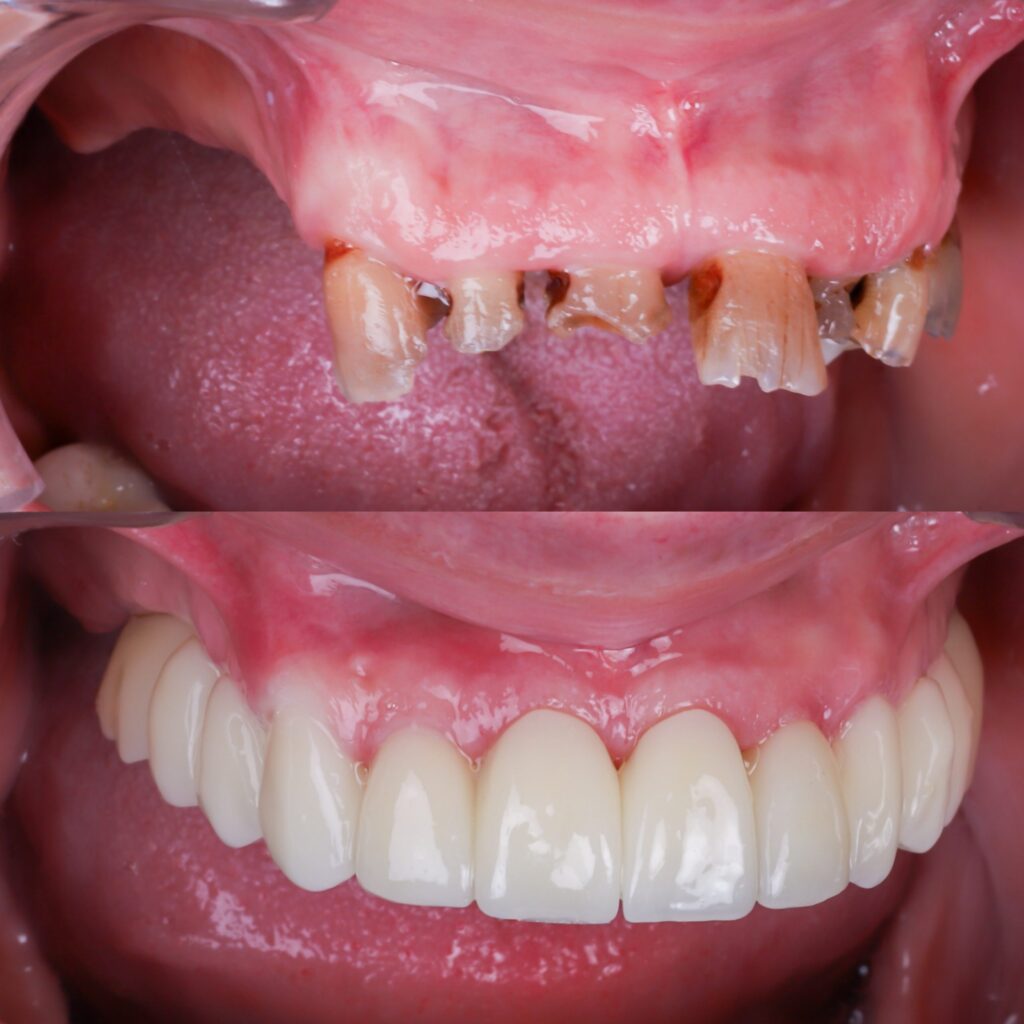

Implantes dentales en Madrid – calidad y precio en Barrio Salamanca En Dr. Alejandro Prieto Dental Clínica Dental, tu clínica dental de confianza en el Barrio Salamanca de Madrid, somos expertos en implantes dentales de todos los tipos. Mezclamos implantología avanzada con alta estética. Si estás buscando una solución duradera, estética y con precios competitivos, […]